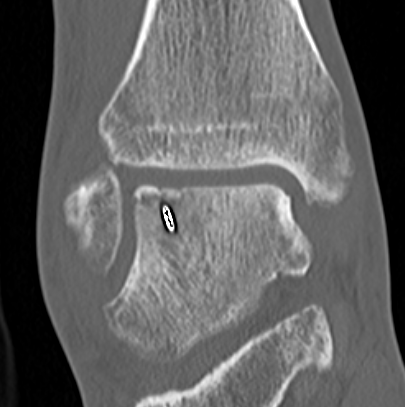

CT

Stage III

Stage IV displaced fragment with osteochondral defect